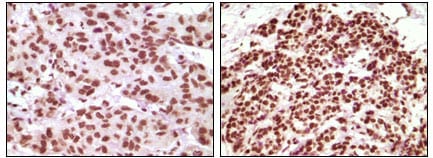

分类: 科研抗体货号: 20107别名: PR; NR3C3; PGR应用: IHC反应种属: Human